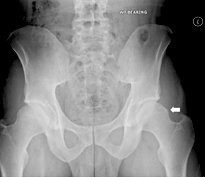

AP pelvis demonstrates pistol-grip deformity (arrow).

Cam impingement demonstrates an aspherical femoral head with a predominate "bump," often referred to as a pistol-grip deformity. The cam impingement is more common in young males. These osseous bumps lead to a decreased femoral head-neck offset, which is defined by the distance between the widest diameter of the femoral head and the most prominent part of the femoral neck. It is thought that the main cause of cam impingement is growth abnormalities of the capital femoral epiphysis.